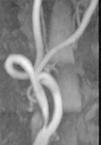

Fig. 3. --(A) Imagen de reconstrucción volumen rendering. (B) Reconstrucción mini-MIP de la arteria carótida izquierda. Estudio de angio-CT donde se observa la bifurcación carotídea y la porción proximal de ACI sin ninguna estenosis de significación.